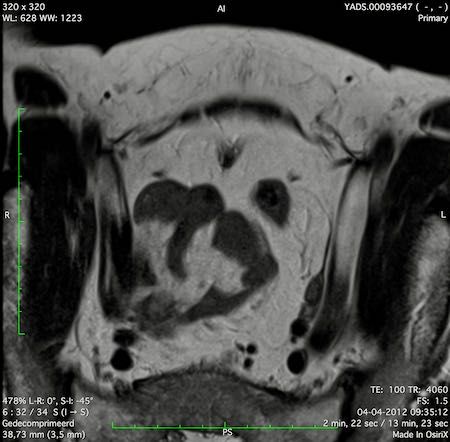

Hình ảnh

Các hình ảnh được cung cấp cho thấy ung thư biểu mô tế bào nhẫn với tình trạng dày lan tỏa thành trực tràng, hình ảnh bia bắn điển hình, và sự xâm lấn mỡ mạc treo trực tràng.